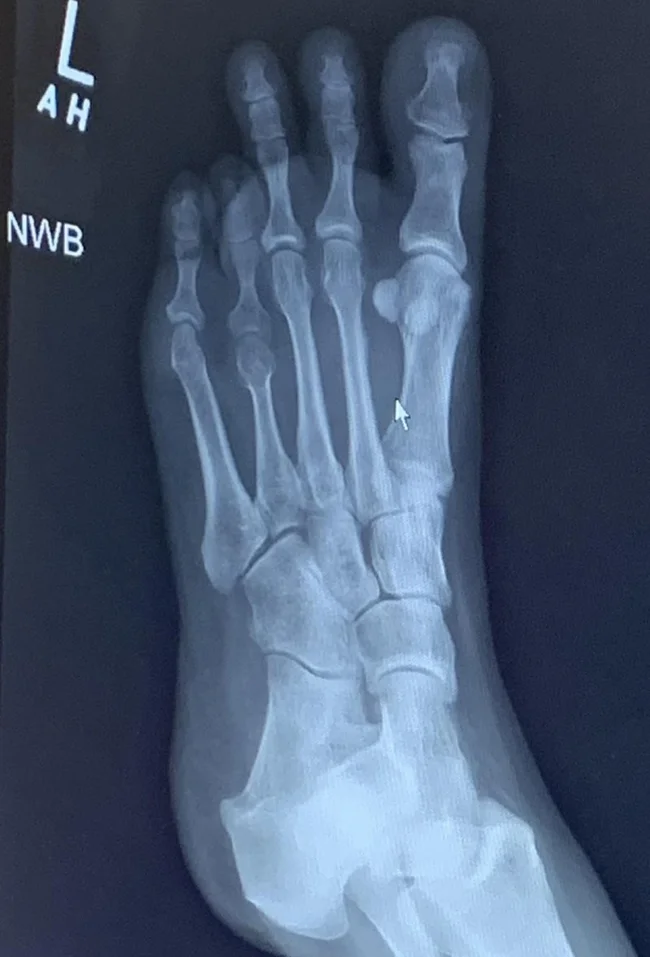

Вроде бы обычный снимок, но обратите внимание на пальцы